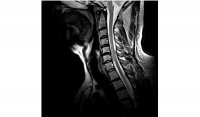

How bad is that? Is that a pinched cord I'm lookin' at?I didn't stay at Holiday Inn Express so I am going to leave this up to the Dr's......

It looks like there is some pressure on the cord at C-5. A fractured vertebra? It probably hurts, but I don't think it'll need surgery.I didn't stay at Holiday Inn Express so I am going to leave this up to the Dr's......

So far the consensus. My Chiropractor and the Technician. Will see the neurosurgeon shortly.It looks like there is some pressure on the cord at C-5. A fractured vertebra? It probably hurts, but I don't think it'll need surgery.